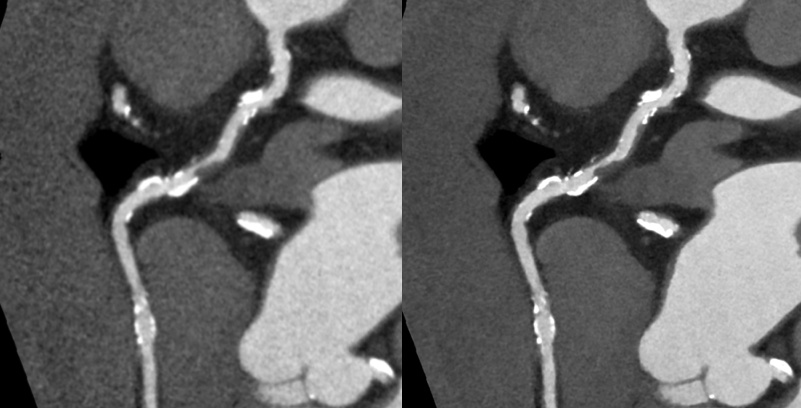

キヤノンメディカルシステムズが開発したPrecise IQ Engine(PIQE)によるディープラーニングの画像によって、冠動脈CT検査で評価が難しい石灰化やステントに接する部分の描出が向上されるため、さらに正確な画像診断が可能となりました。

サブトラクション冠動脈CT

これまで、CTでは評価が難しいとされている冠動脈の強い石灰化部位やステント治療部位において、我々が考案した特殊な撮影(test bolus tracking法)および画像処理技術を用いて評価可能な画像を可能な限り提供しています。

Yamaguchi T. Ichikawa K, Takahashi D. et.al. A New Contrast Enhancement Protocol for Subtraction Coronary Computed Tomography Requiring a Short Breath-Holding Time. Academic Radiology Published online: October 17, 2016